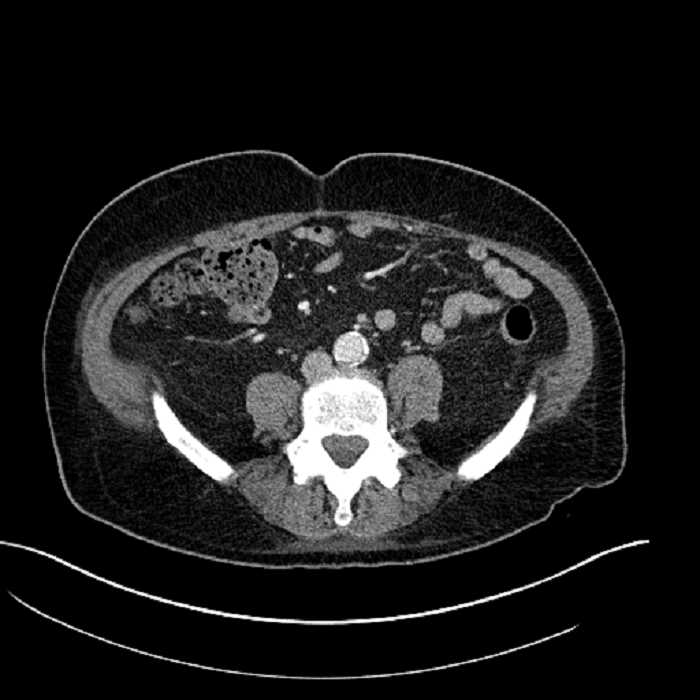

• Large fluid density structure in hepatic segments 7 and 8 measuring 10 x 7 x 7 cm with internal septation and circumferential ill-defined low density compatible with edema

• Peripherally enhancing subcapsular collections along the anterior margin of the left hepatic lobe measuring 3 x 1 cm and 2 x 1 cm

• Clearly marginated fluid density structure in segment 7 and several other scattered tiny hypodensities, which likely represent cysts

• Mild mural thickening of a segment of the sigmoid colon with adjacent fat stranding and a 1.5 cm fluid and gas collection along the tip of an inflamed diverticulum

• Loss of the normal fat plane between this collection and adjacent loops of small bowel, which demonstrate mural thickening

• High grade stenosis of the left common iliac artery, with the left internal and external iliac arteries remaining patent

Acute sigmoid diverticulitis complicated by a small contained perforation and a large abscess in the right hepatic lobe. Additional small subcapsular abscesses along the anterior margin of the left hepatic lobe.

Additionally, loss of the normal fat plane between the peridiverticular collection and adjacent thickened loops of small bowel raises the potential for an enterocolonic fistula.

High grade stenosis of the left common iliac artery. The left external and internal iliac arteries are patent.

• The classic CT imaging appearance is a double target sign with internal low density surrounded by an internal enhancing rim (capsule) and a low density external rim (edema)

Hepatic abscess showing the double target sign with low density internally surrounded by a thin inner enhancing rim (red arrow) and ill-defined outer low density rim (yellow arrow). Blue arrow indicates an internal septation. Red arrows: additional smaller subcapsular abscesses. Red arrow: focal contained perforation associated with diverticulitis.